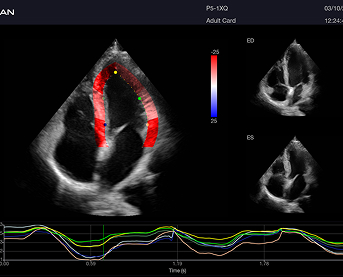

Incluye además eLV para análisis cardíaco avanzado, eOB para mediciones obstétricas automáticas y eLearn como guía interactiva.